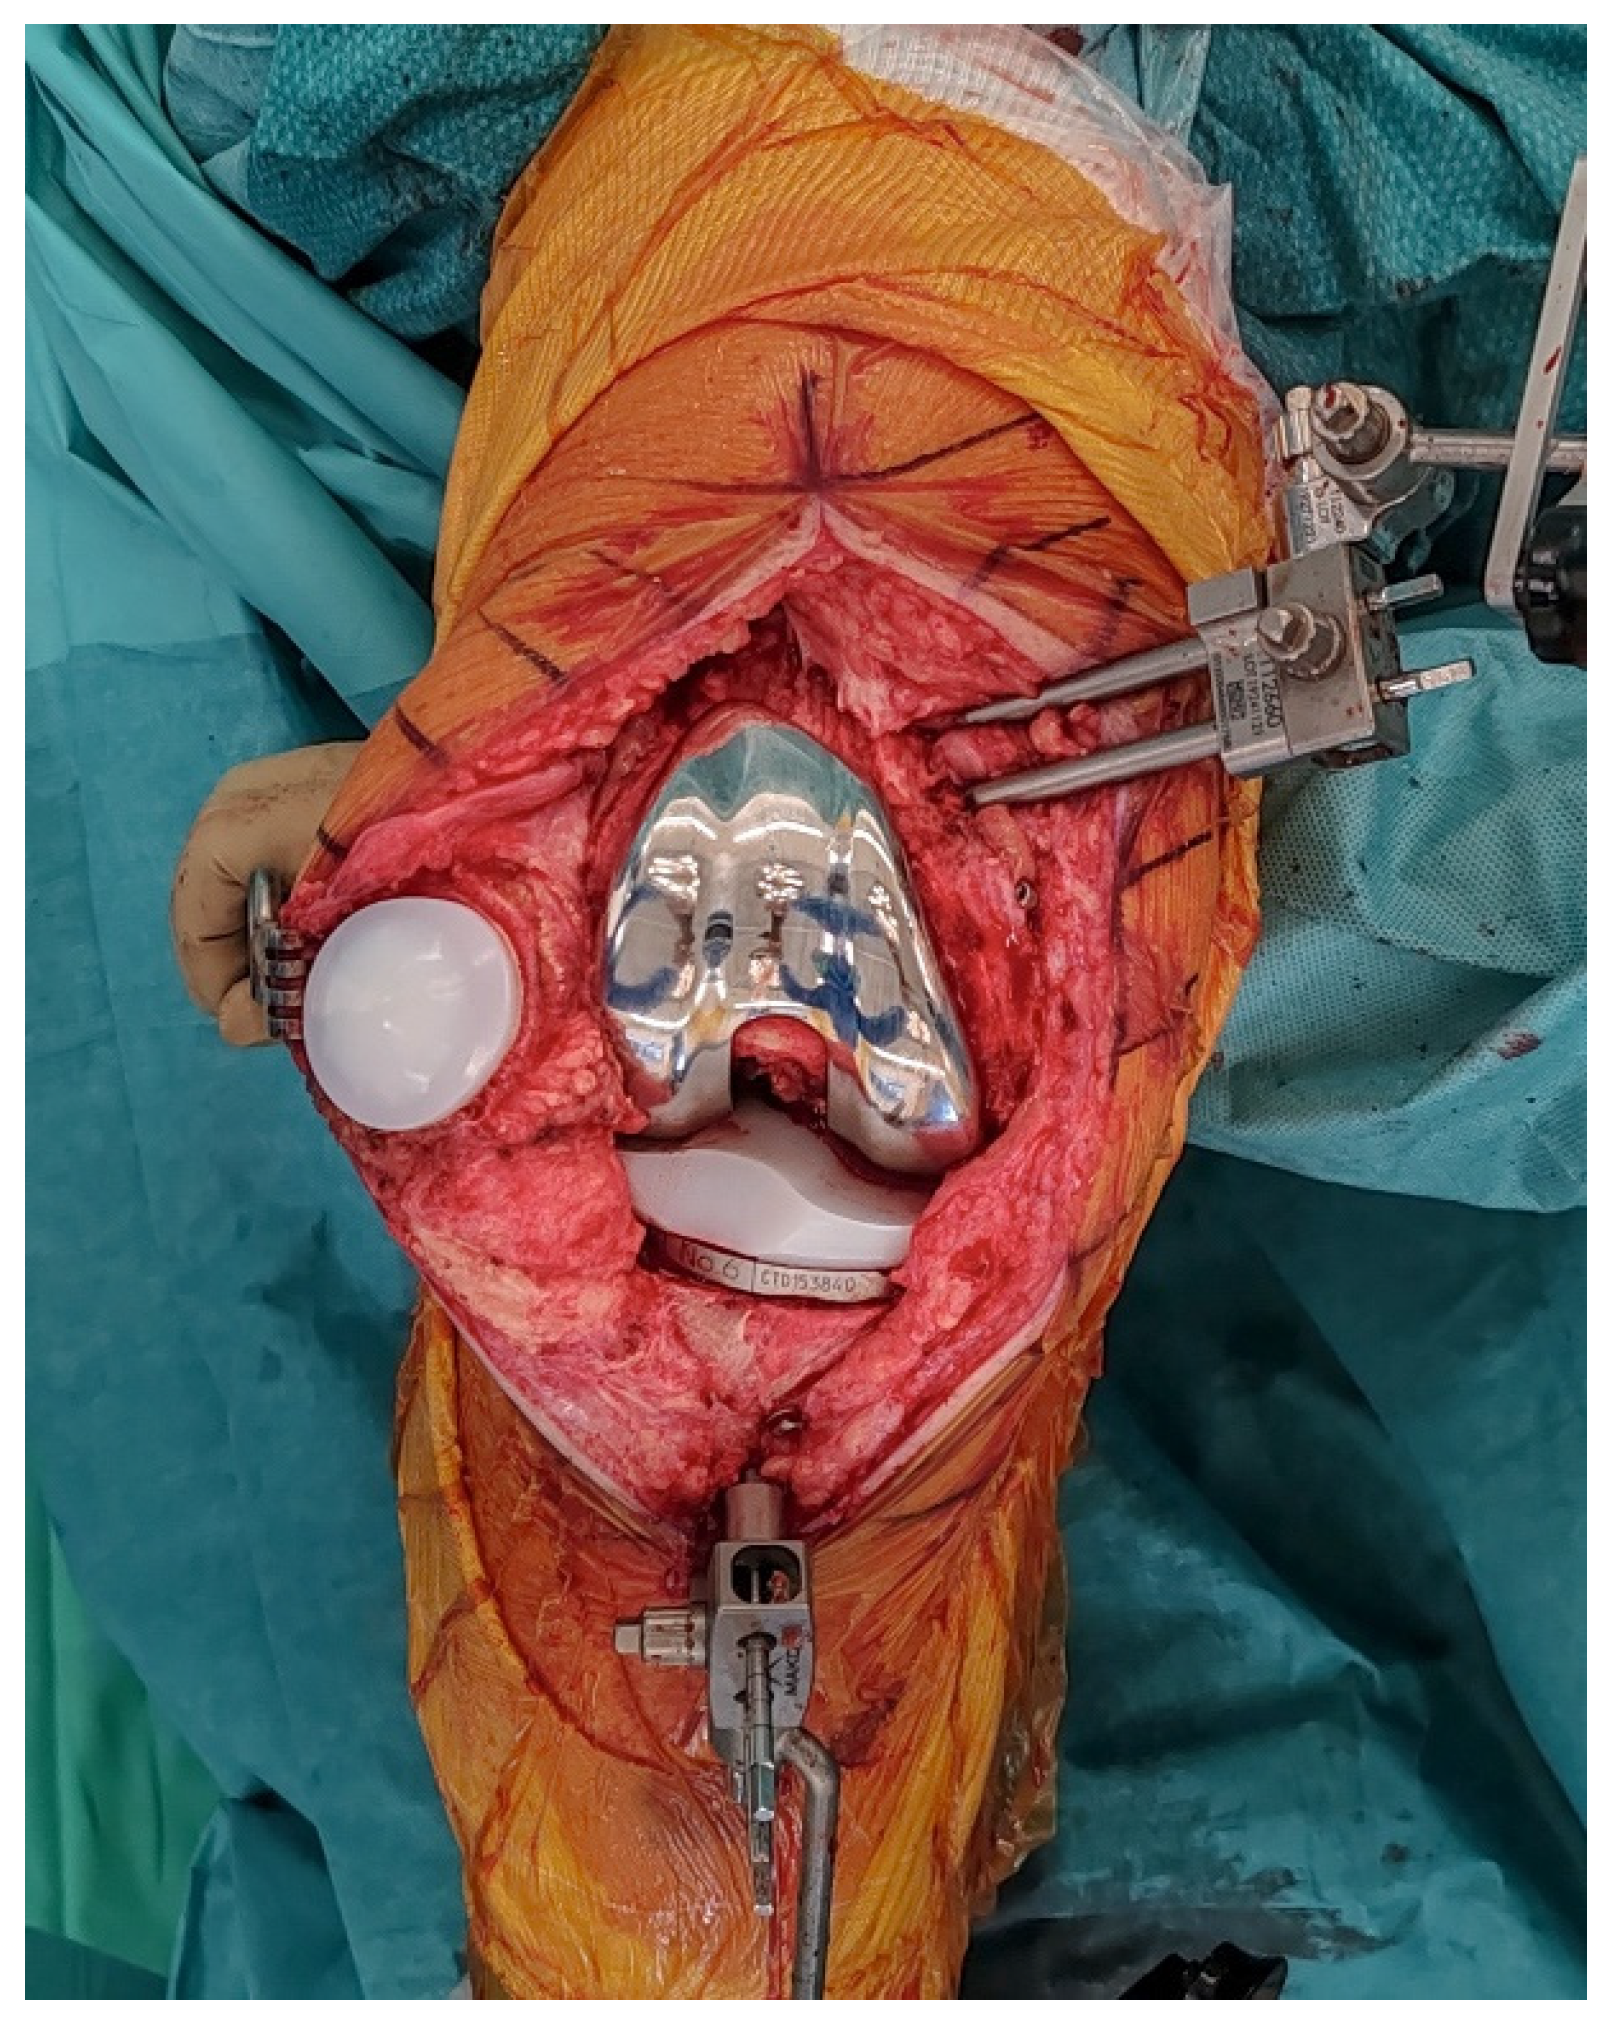

2.3. Pins Placement and Landmark Registration

Array pins for the robotic system are inserted according to protocol (4 mm femur, 3 mm tibia) through the same medial parapatellar incision to minimize soft-tissue trauma (Figure 1). Before explantation, registration is performed using the central sagittal axis of the in situ UKA components to limit the impact of CT metal artifacts (Figure 2). On the femoral component, this axis is marked with a dermographic pen. The polyethylene insert is removed solely to expose reference surfaces. Registration landmarks are acquired directly on the in situ metal components, along the pre-marked central sagittal axis (used as a surrogate of the native medial condyle) to improve mapping accuracy. The polyethylene insert is reinserted immediately afterward to allow dynamic balance assessment. Pin stability is verified prior to proceeding, because any motion can compromise tracking accuracy throughout the procedure. Registration accuracy is confirmed with checkpoint validation. If any control checkpoint exceeds 0.5 mm, landmarks and checkpoints are repeated until all residuals meet tolerance. Osteophytes are left in place during registration and removed only afterward to avoid altering reference points.

Figure 1.

Intraoperative view after medial parapatellar approach reusing the previous incision and arthrotomy, showing the medial unicompartmental knee arthroplasty (UKA) in situ with array pins in place, prior to registration and component removal.

Figure 2.

The polyethylene insert is removed to access reference surfaces. Registration landmarks are then acquired directly on the in situ metal components along the marked central sagittal axis.